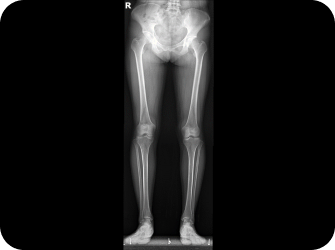

전신 엑스레이 검사

다리길이 엑스레이 검사

해당 사진은 수정없는 실제 치료사진입니다.

환자의 치료결과는 환자의 상태, 치료방법 등에 따라 차이가 발생할 수 있습니다.